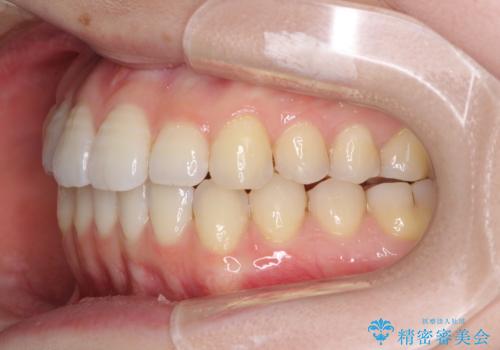

オープンバイトのインビザラインを用いた再矯正

- 矯正治療の後戻りを気にして来院された患者様です。

オープンバイト(前歯の開咬)と下顎骨の偏位による不正咬合が認められました。

骨格の偏位による不正咬合は改善しきれないことを理解いただいた上で、インビザラインにて矯正治療を行うこととしました。

オープンバイトは後戻りを起こしやすいため、極力そのリスクを軽減するため、奥歯を圧下させるように治療を進めていきました。

下顎骨の偏位が顕著であったため、上下の正中を合わせることはできませんでしたが、患者様には大変満足していただきました。